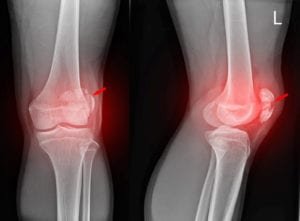

X-ray image of a fractured patella

The patella, more commonly known as the kneecap, sits at the front of your knee and covers the joint. Its underside is covered with cartilage that helps your knee’s various muscles and bones move smoothly as you walk. It also protects your knee joint from violent impacts and injuries.

It is this protective placement of the patella that makes it vulnerable to injuries. Often, when people trip and fall they fracture their patella when landing on their knees.

Patella fractures can make movement of the knee excruciatingly painful and even damage the delicate tendons in the knee, sometimes requiring surgery to put everything back where it belongs.

He is taken to the hospital, where x-rays show that he broke his patella in two places.  The edge of the broken bone has also partially cut through some of the tendons around his knee. George will need surgery to repair the damage.